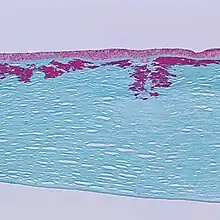

| Reis-Bücklers corneal dystrophy. Reticular opacity in the superficial cornea | |

Reis-Bücklers dystrophy causes a cloudiness in the corneas of both eyes, which may occur as early as 1 year of age, but usually develops by 4 to 5 years of age. It is usually evident within the first decade of life. This cloudiness, or opacity, causes the corneal epithelium to become elevated, which leads to corneal opacities. The corneal erosions may prompt attacks of redness and swelling in the eye (ocular hyperemia), eye pain, and photophobia. Significant vision loss may occur.

Patients with Reis-Bücklers dystrophy develop a reticular pattern of cloudiness in the cornea. This cloudiness, or opacity, usually appears in both eyes (bilaterally) in the upper cornea by 4 or 5 years of age. The opacity elevates the corneal epithelium, eventually leading to corneal erosions that prompt attacks of ocular hyperemia, pain, and photophobia. These recurrent painful corneal epithelial erosions often begin as early as 1 year of age.[1]

With time, the corneal changes progress into opacities in Bowman's layer, which gradually becomes more irregular and more dense.[1] Significant vision loss may occur.[2] However, vascularization of the cornea is not present.[2]